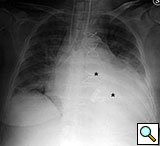

Figure 11. Fourteenth postoperative day image showing sternal wire migration in the caudal sternum segment (*).